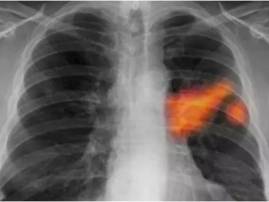

油烟污染与肺结节形成的潜在关联探究

你知道吗?最近有个话题在朋友圈里炒得火热,那就是肺结节的形成可能与油烟有关。是不是觉得有点不可思议?别急,让我带你一探究竟,揭开这个神秘的面纱。油烟,那个看不见的“隐形杀手”想象厨房里弥漫着各种美食的香气,而你正忙碌地烹饪着。这时,你是否注意到,锅里升腾的油烟在空气中飘荡?这些看似无害的油烟,其实可能隐藏着巨...